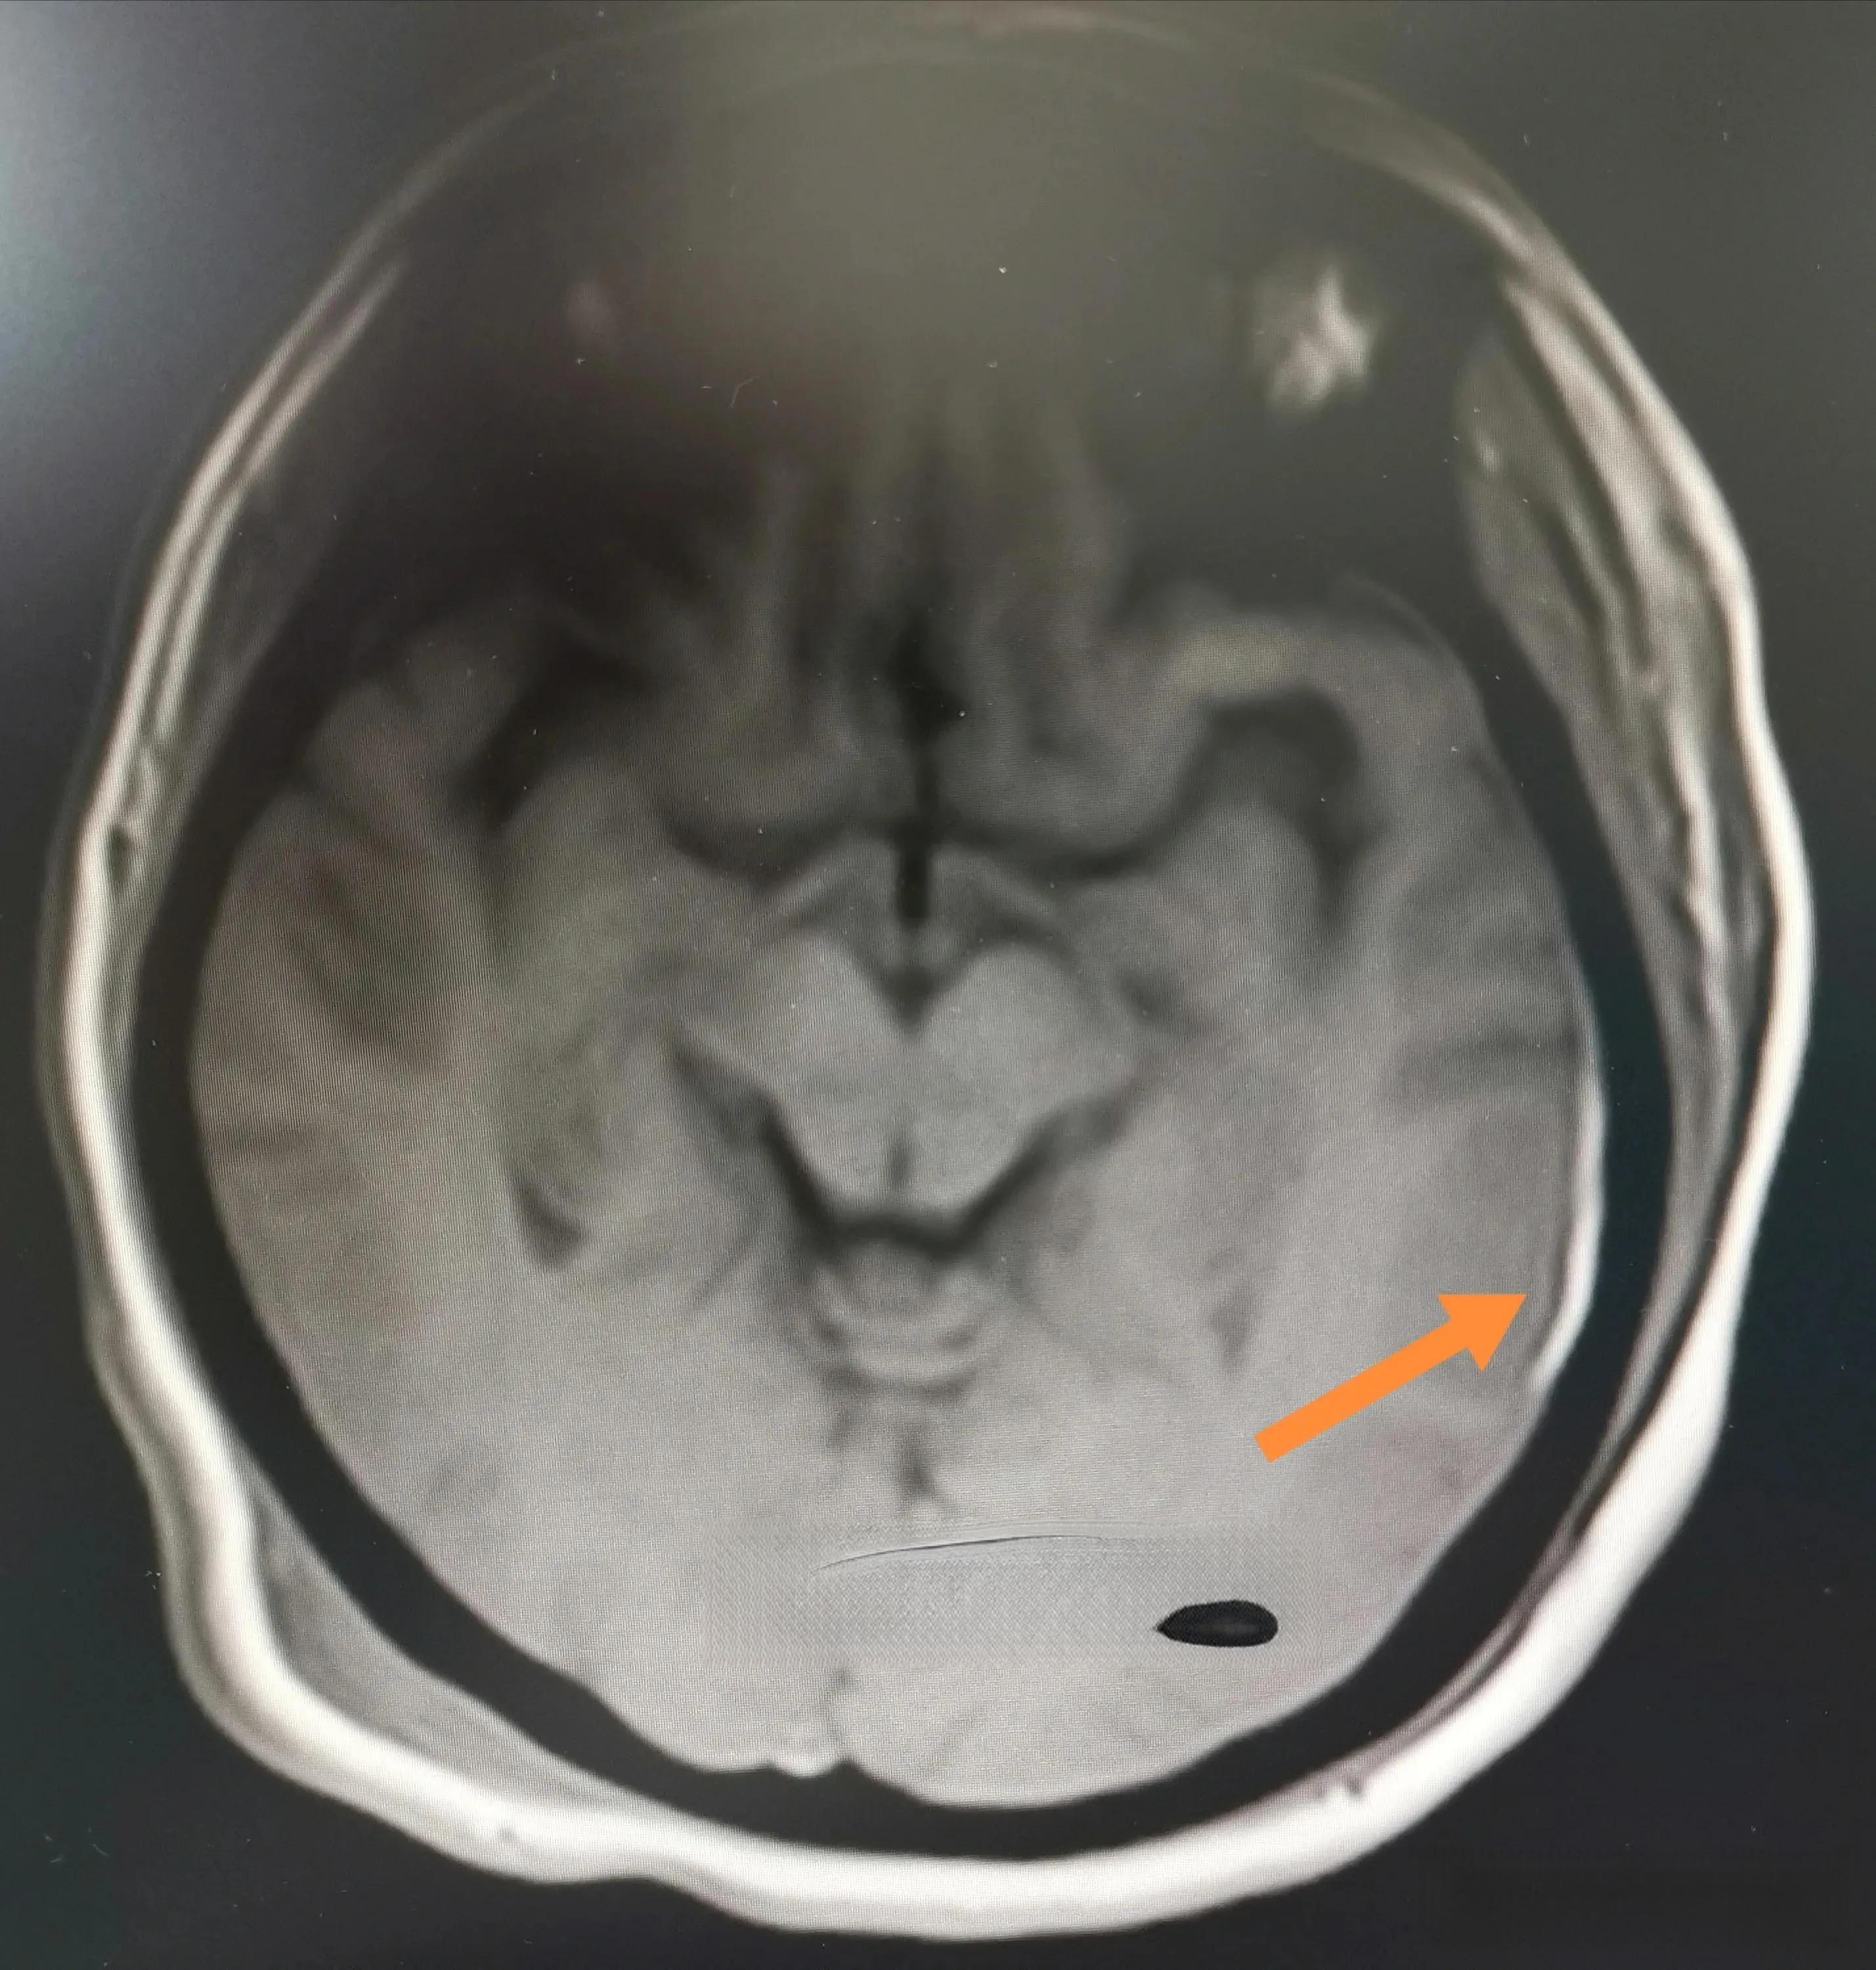

Image